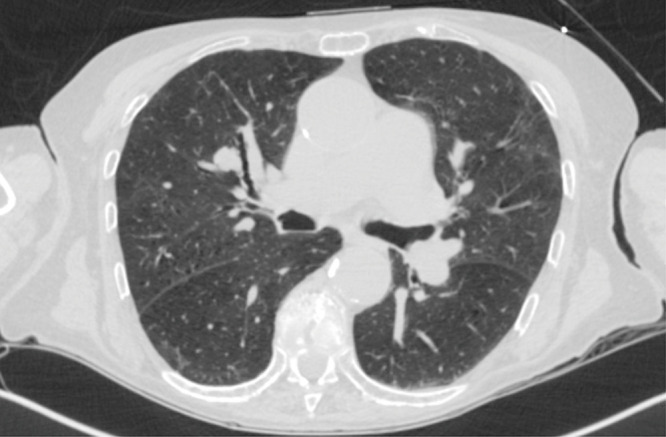

Navigational bronchoscopy is increasingly used to target peripheral pulmonary nodules using electromagnetic navigational platforms (ENB), fluoroscopic navigation, or robotic-assisted bronchoscopy. The selection of equipment largely depends on the availability of technology, expertise, and the characteristics of the nodule and patient. Radial EBUS (r-EBUS) is often combined with these techniques for real-time confirmation of the nodule location. A bronchus sign is considered to have a higher diagnostic yield when biopsy tools can directly reach the nodule. We describe a case series of creating a false airway into the nodule when an eccentric r-EBUS signal is seen to subsequently obtain a concentric signal.

Abstract Image